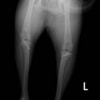

■ 症例20 ポメラニアン 8ヶ月 1.8kg

左右膝蓋骨脱臼 グレードⅢ

2ヶ月前から間欠的跛行が認められ、両膝の膝蓋骨脱臼整復術を行った。

手技は縫工筋及び内側広筋の解放、脛骨粗面の外側転位、滑車ブロック形造溝術、内外側関節包の縫縮を選択し実施した。

右側の膝蓋骨脱臼は上記手技で整復されたものの、左側はそれのみでは膝蓋骨が浮く様子が認められた。その為、PDS縫合糸にて膝蓋靱帯を1糸のみ縫合し、靱帯の縫縮を行った。

膝蓋骨脱臼は膝関節における膝蓋骨の内外側の脱臼と定義されるが、時として単純な内外の脱臼ではなく、膝蓋骨が大きく前方に浮き上がるように脱臼する場合がある。特にトイプードルやポメラニアンといった犬種に多く認められる。

内側脱臼に加えて前方への浮き上がりを矯正する為に、従来より脛骨粗面転移により膝蓋靭帯を外方と下方に引っ張り、固定する方法を選択する。膝蓋骨の前方への浮き上がりが軽度の場合は、従来法ではなく関節包の縫縮で対応していた。しかし、一部の症例で膝蓋骨の動きが悪くなり伸展機構が円滑に機能せずロボット様歩行になるケースがあった。

その為、膝蓋靭帯自体を縫縮する方法を採用した。この方法により、膝関節の伸展機構を妨げず膝蓋骨の軽度の浮きを矯正することが可能となった。

本症例の経過は良好である